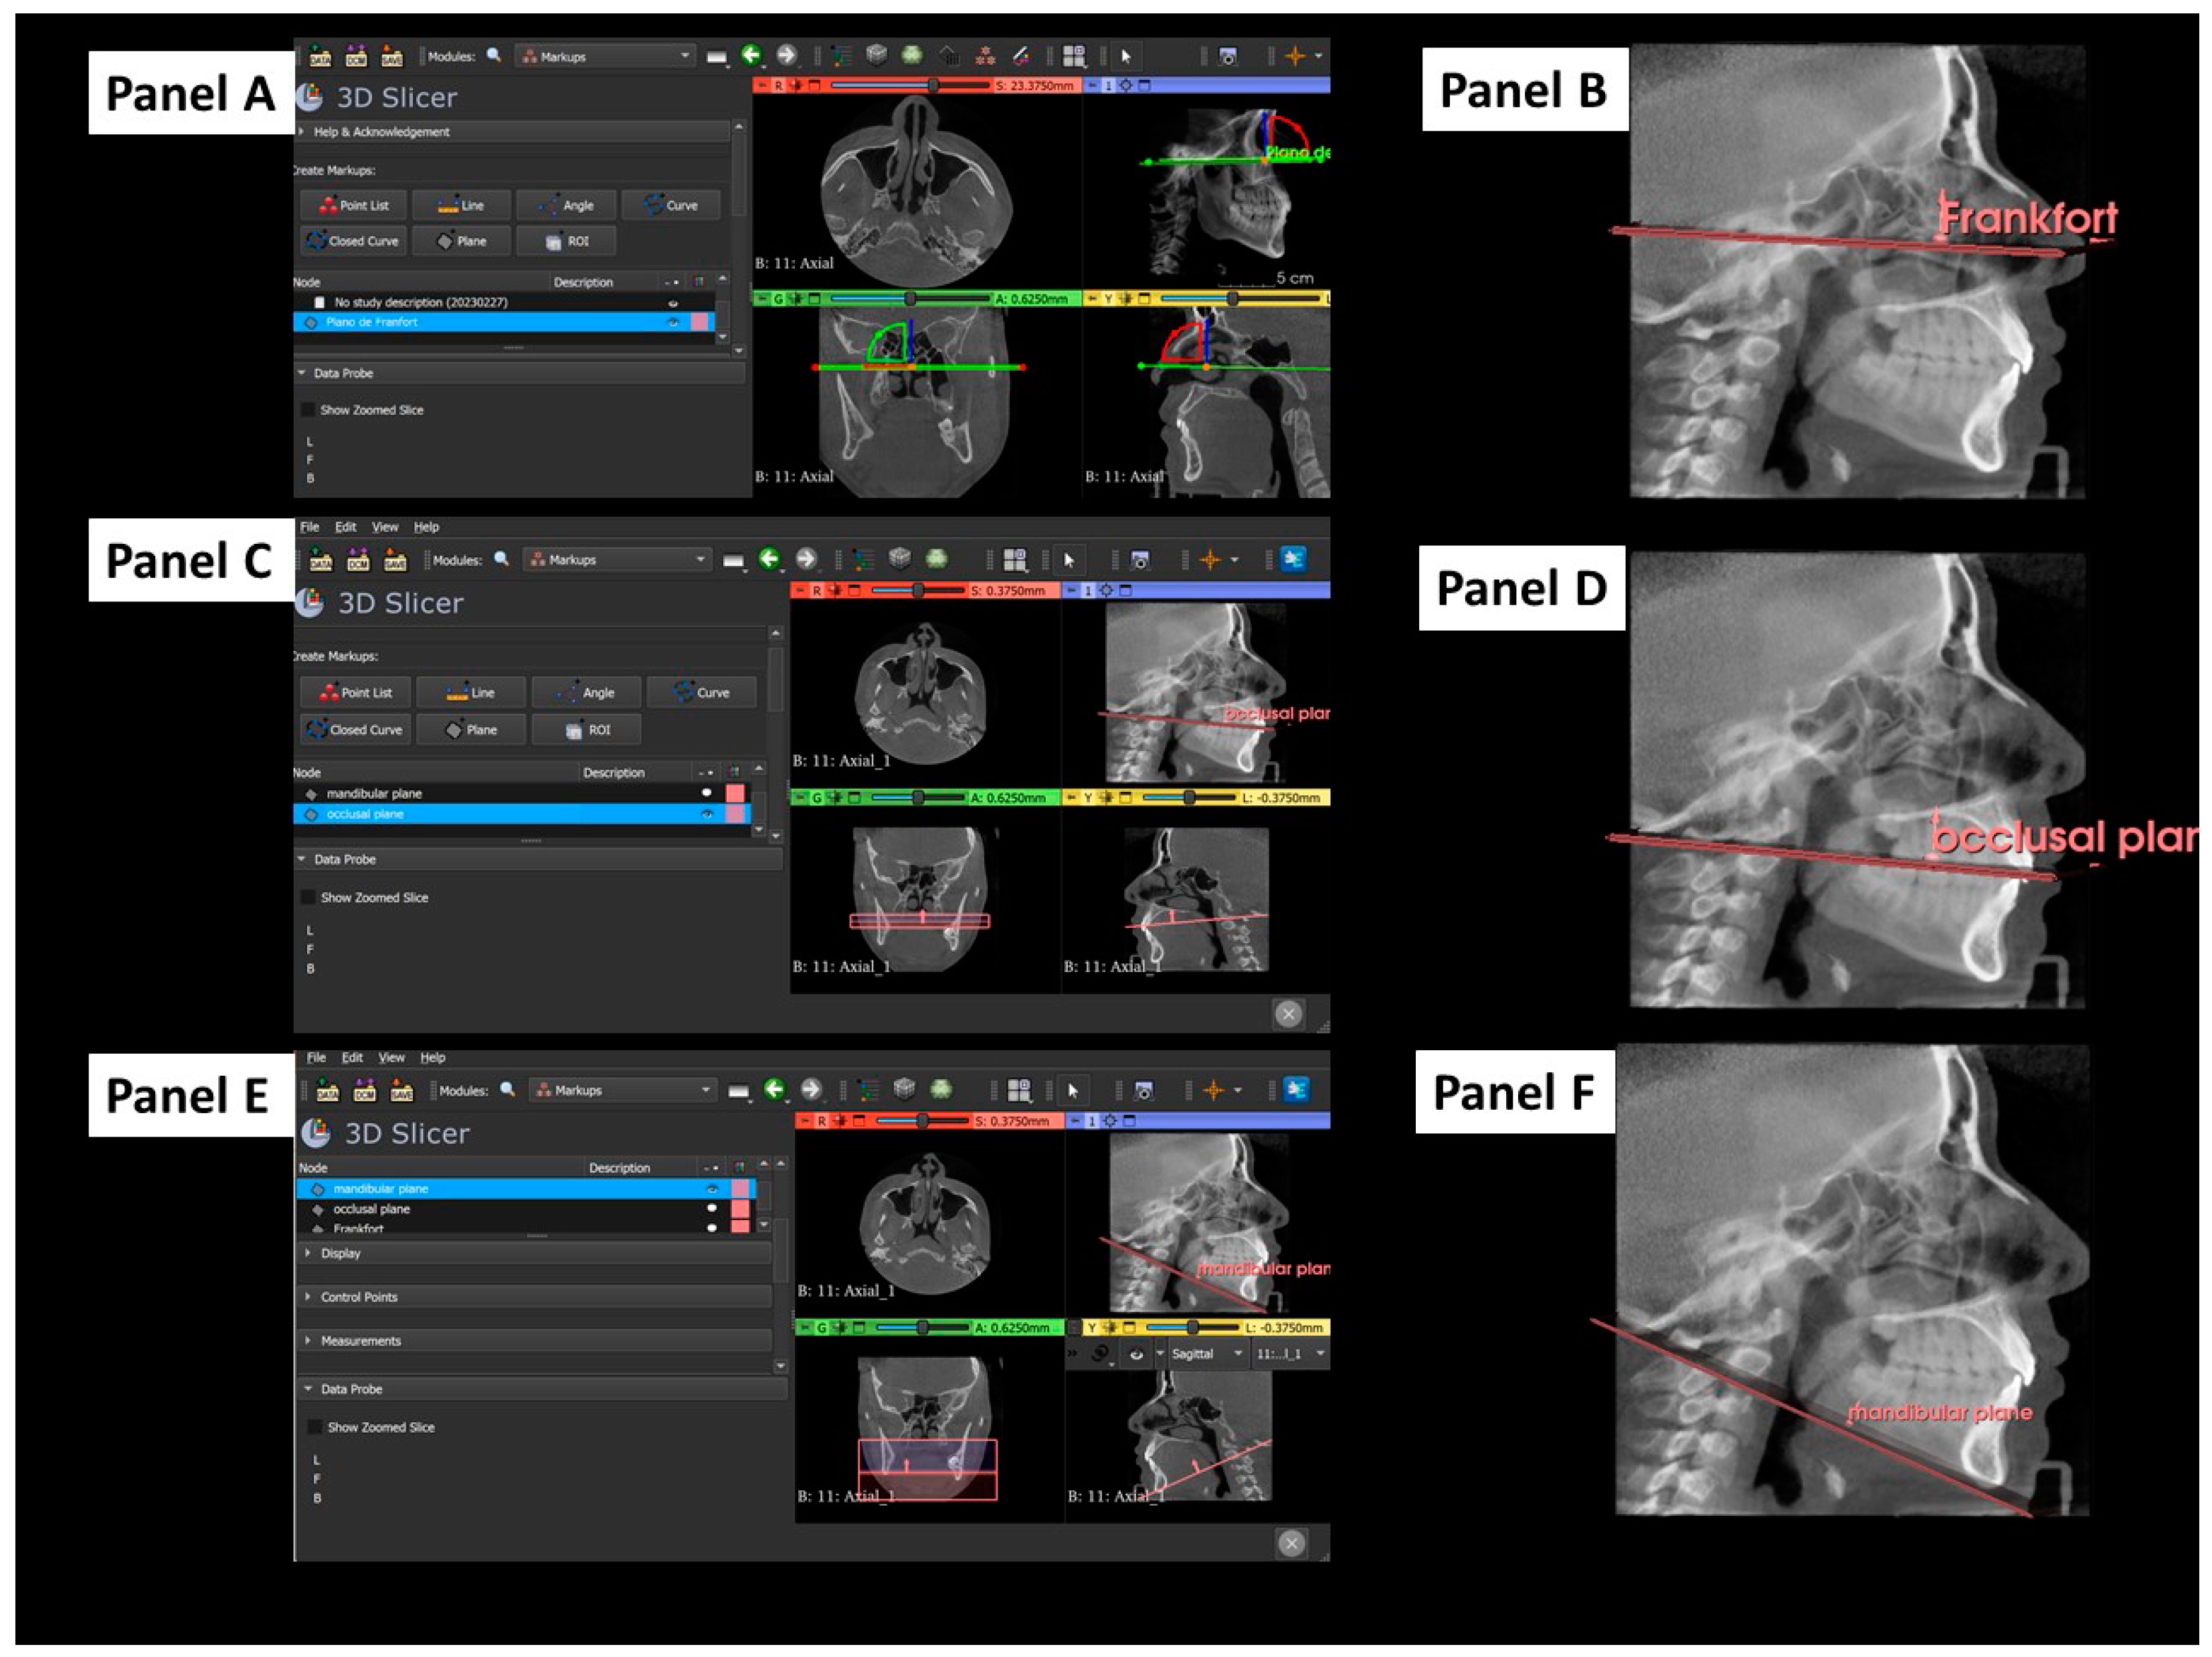

2.3. Tridimensional Reference Planes

2.4. Outcome and Independent Variables